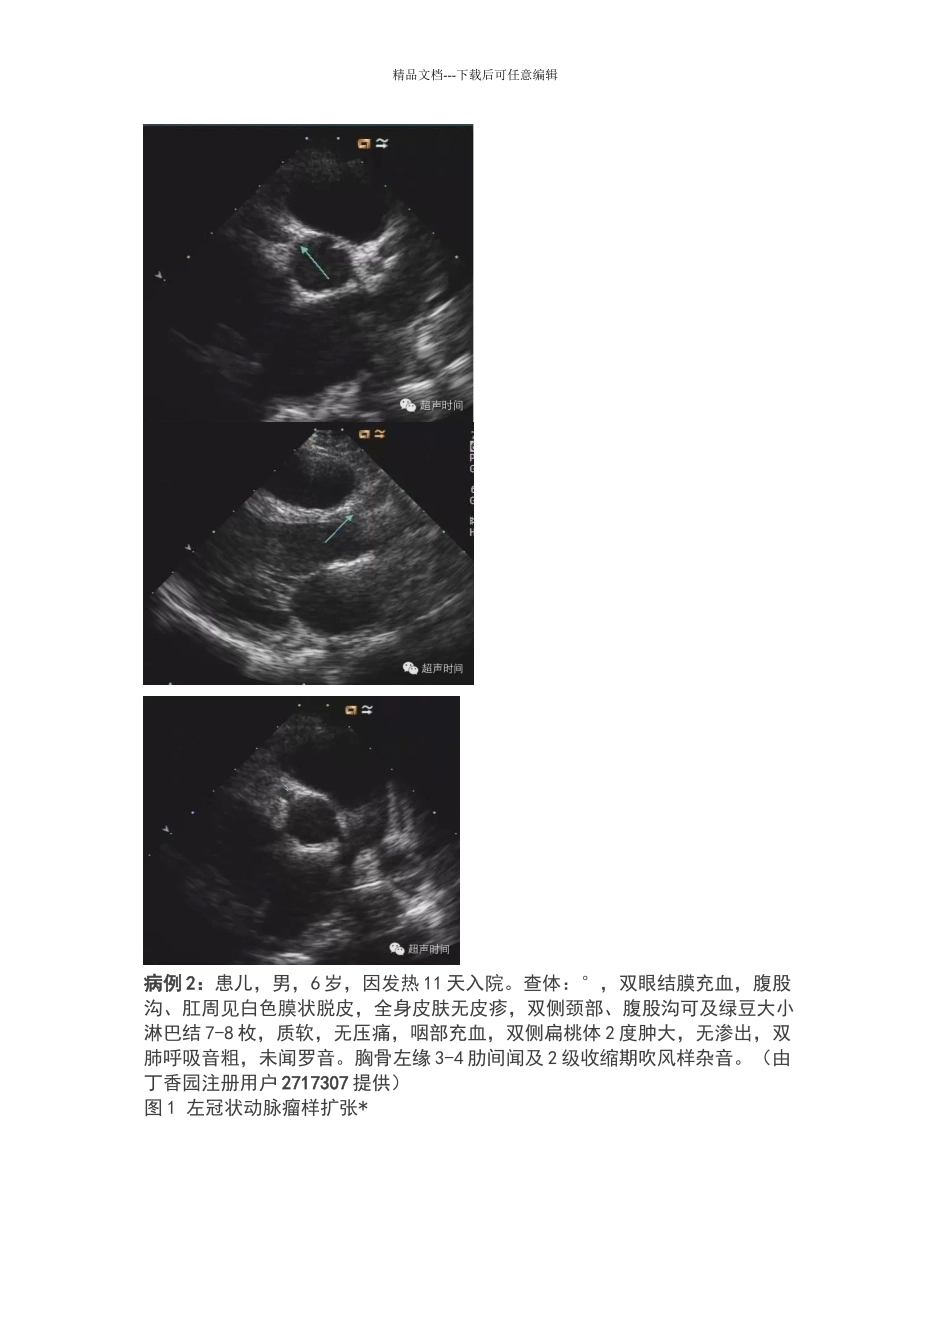

精品文档---下载后可任意编辑川崎病累及冠状动脉的超声表现川崎病1、皮肤粘膜淋巴结综合征是 1967 年由日本川崎富作最早发现,故命名为川崎病。(提问:有没有以中国人名字命名的疾病)2、本病的发病原因至今未明。3、基本病理变化:全身性血管炎,常累及冠状动脉及其分支。诊断标准1、发热 5 天以上;2、手足症状:末端梭形肿胀,热退脱皮;3、皮肤多形红斑;4、粘膜改变:口腔粘膜牛肉色,球结膜充血;5、口唇干裂,杨梅舌;6、非化脓性颈部淋巴结炎。 包括发热在内共有 5 条,无需实验室支持即可确诊;如有超声提示冠状动脉改变,包括发热在内共有 4 条即可确诊,但此时要排除其它疾病:如风湿热(抗O 增高)。6 条可概括为:发热、皮肤、粘膜、淋巴结、口舌、手足。超声相关超声主要用于发现患儿冠状动脉有无病变,二维及彩色多普勒超声心动图可显示典型病例的冠状动脉异常扩张或冠状动脉瘤。小儿冠状动脉内径正常参考值不同的资料给出的正常值不同,以下数值供大家参考:精品文档---下载后可任意编辑1、4 周-3 岁为,3-9 岁为 3mm,9-14 岁为。2、儿童正常冠状动脉内径正常参考值范围(由丁香园注册用户阿然 0 提供)3、正常儿童左右冠脉主干内径(mm)(郑慕白、郭文彬等主编《超声心动图综合解析与诊断》)年龄....................左冠状动脉.................右冠状动脉新生儿................. ........................ 岁....................... .........................岁.......................岁 ......................岁...............小儿冠状动脉扩张标准1、扩张标准:(1)内径大于正常值倍,或(2)冠状动脉与主动脉根部内径之比(CA/Ao)>。2、扩张程度:0 级:正常范围1 级(轻度):<4mm2 级(中度):4-7mm,此级最常见3 级(重度):≥8mm,可累及主干 1 支以上冠状动脉瘤:冠状动脉发生局部性或弥漫性扩张,超过局部原来直径的两倍以上,呈球形、纺锤样改变。典型病例病例 1:患儿,女,6 岁,发热一周就诊。眼部结膜充血。口唇、手指未见明显异常(由丁香园注册用户 ciwawa2 提供)精品文档---下载后可任意编辑病例 2:患儿,男,6 岁,因发热 11 天入院。查体:°,双眼结膜充血,腹股沟、肛周见白色膜状脱皮,全身皮肤无皮疹,双侧颈部、腹股沟可及绿豆大小淋巴结 7-8 枚,质软,无压痛,咽部充血,双侧扁桃体 2 度肿大,无渗出,双肺呼吸音粗,未闻罗音。胸骨左缘 3-4 肋...